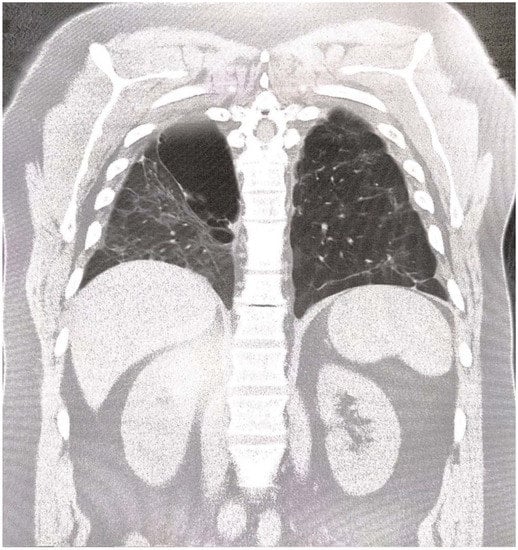

Spontaneous Post-COVID-19 Pneumothorax in a Patient with No Prior Respiratory Tract Pathology: A Case Report

2. Case Report